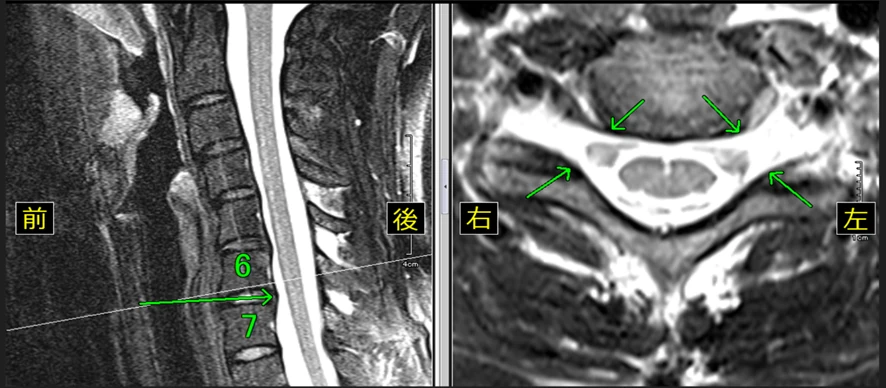

【14級レベルの頚椎のMRI画像】

※頚椎椎間板の軽度の膨隆が認められます。